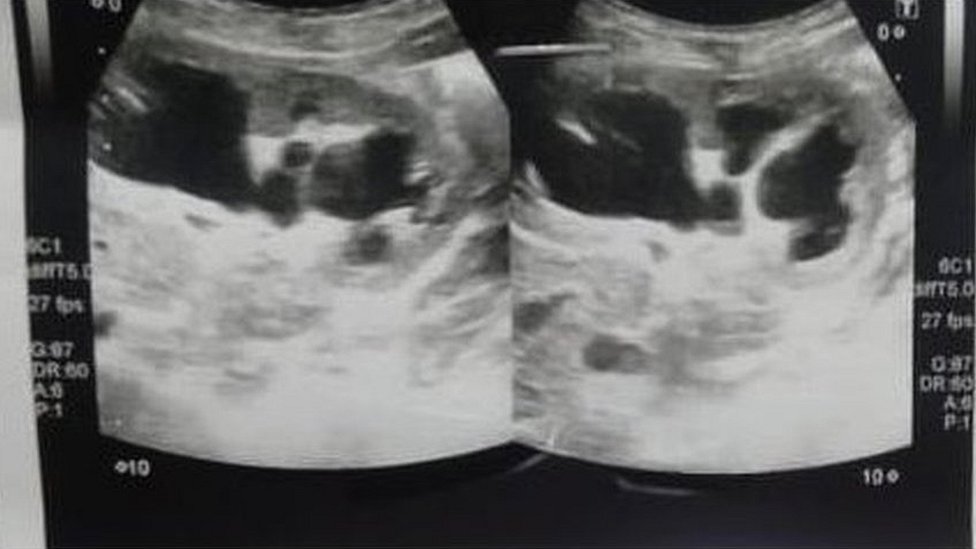

„Kad sam pregledao bebu, napipao sam neku vrstu tumora.

„Uradio sam ultrazvuk i postavio dijagnozu neke vrste ciste u abdomenu.

„Nisam uopšte razmotrio mogućnost da bi moglo da bude nešto drugo“, kaže on.

Roditelji nisu mogli da priušte magnetnu rezonancu, koja bi omogućila tačniju dijagnozu.

Ali kad je tim lekara došao do zapanjujućeg otkrića o Šazijinoj nerođenoj bliznakinji tokom operacije, 29. avgusta, shvatili su da moraju da izvedu delikatan zahvat uklanjanja fetusa.

„Bili smo zapanjeni kad smo otkrili da ova neuhranjena beba nosi fetus vlastite bliznakinje“, ističe doktor.

Fetus se ponašao kao parazit, spojio se sa bebinim tankim crevima, odakle je crpeo krv i uskraćivao ključne hranljive materije Šaziji.